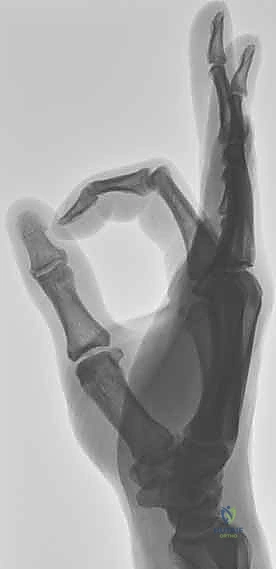

1. الفحص السريري واختبار الإجهاد (Stress Test)

يقوم الدكتور هطيف بإجراء فحص دقيق يتضمن تطبيق ضغط لطيف على المفصل في اتجاهات معينة لتقييم درجة التراخي (Laxity). يتم مقارنة الإبهام المصاب بالإبهام السليم لتحديد مقدار الانحراف الزاوي. إذا كان الانحراف يزيد عن 30-35 درجة، فهذا مؤشر قوي على تمزق كامل للرباط.

2. التصوير بالأشعة السينية (X-rays)

يُعد التصوير الشعاعي الخطوة الأولى لاستبعاد وجود كسور مصاحبة. في كثير من الأحيان، ينسلخ الرباط ويسحب معه قطعة صغيرة من العظم (Avulsion fracture). كما يتم أخذ صور أشعة تحت الإجهاد (Stress X-rays) لتوثيق عدم الاستقرار.